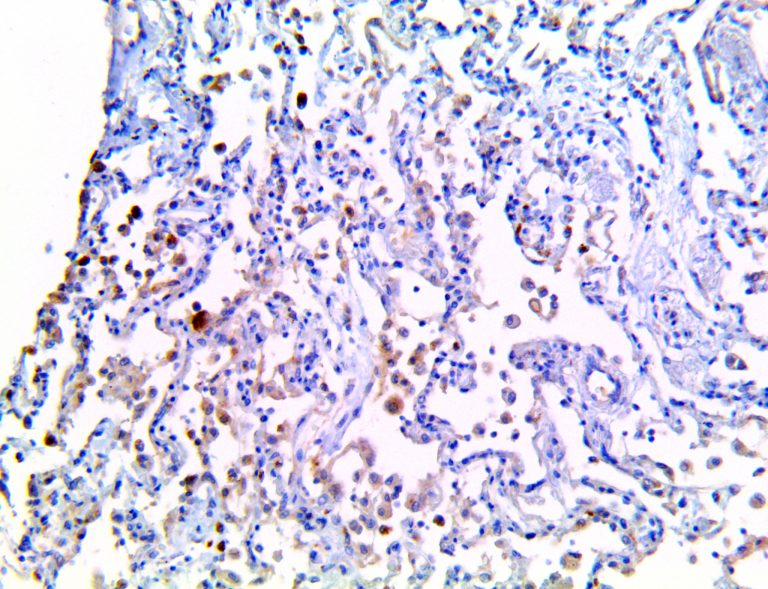

The vast majority of patients with COVID-19 have had a good prognosis, but there are still some critical individuals and even death.10 Most of these critically ill and dead patients do not develop severe clinical manifestations in the early stages of the disease. Some patients only show mild fever, cough, or muscle soreness. These conditions suddenly deteriorate in the later stages of the disease or in the recovery process . Acute respiratory distress syndrome (ARDS) and multiple-organ failure occur rapidly, resulting in death within a short time. Cytokine storm is considered to be one of the major causes of ARDS and multiple organ failure.

Cytokine Storm Syndrome (CSS) is characterized by systemic symptoms and signs derived from a massive and uncontrolled inflammatory response caused by pro- and anti-inflammatory cytokine dysregulation. Viruses, such as Herpes and Epstein-Barr are known to trigger CSS, as is H5N1 influenza. Current literature indicates that SARS-CoV-2 triggers CSS and has been attributed to the severe symptoms’ characteristic of critical patients. CSS in these patients is often fatal, as was the case in the previous SARS and MERS outbreaks.

This activation induces inflammatory monocytes to highly express IL-6, starting a localized and then systemic cascade effect that results in hyperproduction of IL-6, which accelerates the inflammatory process. Because IL-6 also increases vascular permeability, excessive levels cause blood vessels to become very leaky. This, along with clotting factors released from vascular endothelial cells, stimulates the coagulation cascade, resulting in microthrombosis (tiny clots), which leads to ischemia and tissue death of the kidney, intestines, heart, liver, brain and extremities.